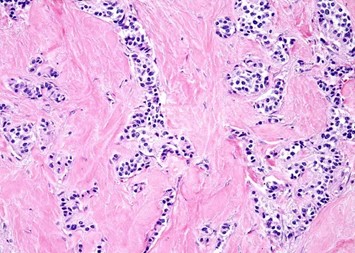

Estudio histopatológico reveló tumor neuroendocrino bien diferenciado grado 1, márgenes libres con ausencia de metástasis.

Estudio histopatológico reveló tumor neuroendocrino bien diferenciado grado 1.

Estudio histopatológico reveló neoplásica de estirpe neuroendocrina bien delimitada.